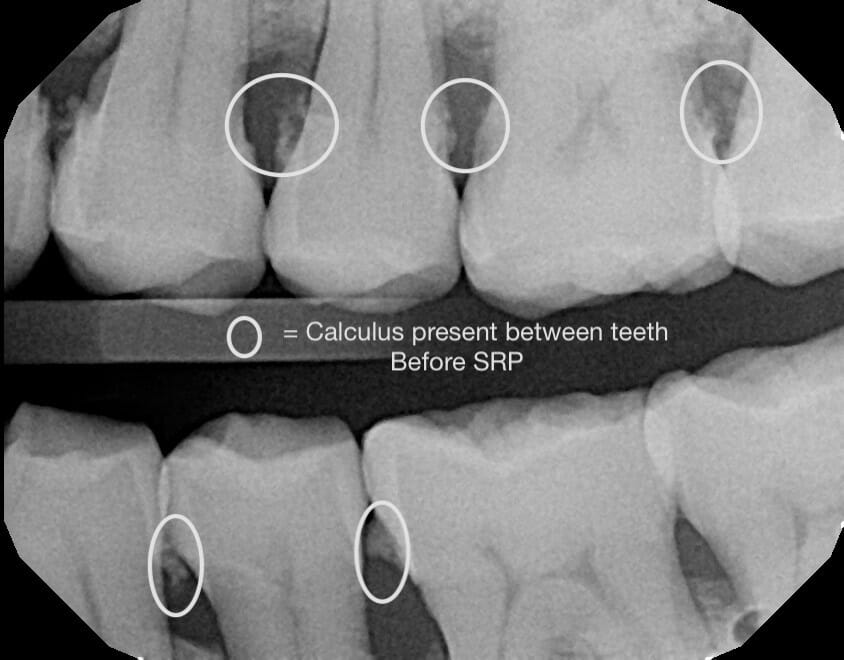

![]()

One of our two awesome hygienists (Ciera or Edith) will remove the bacteria from underneath your gums. Once this is done, your gums will have a higher likelihood of shrinking back to a healthier, more stable, state.

This will also help to reduce or eliminate the bleeding you experience while brushing, while at the same time improving your overall gum tissue health – which will ultimately help to keep all of your current teeth present and in the correct place.

Following our assessment, we’ll use a few injections of anesthetic to numb your teeth and gums. Then we will use our water pressure tool to clean out the bacteria before doing our final assessment, and maybe taking some additional X-rays to make sure we’ve removed all of the bacteria.

Because the bacteria have built up over (in many cases) years below your gums, once that bacteria is gone, it’s common to feel like you have holes between your teeth or even cavities in them. Don’t worry – that’s not the case!

What’s true is that so much bacteria has been removed so that your gums can shrink back to a healthy size. Although the feeling is a “weird” one – it’s a great sign that you’ve just made tremendous progress.